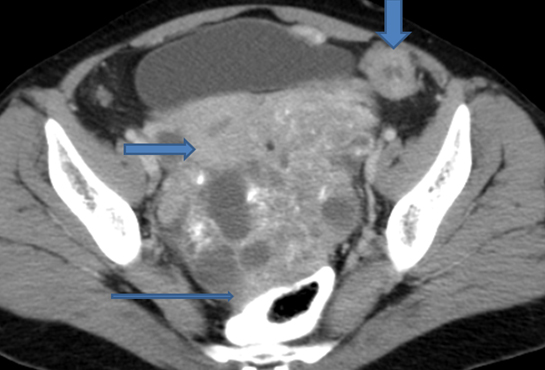

Stage 2: Tumour extends to pelvic soft tissues, or organs in pelvis. In stage 2a extension to uterus and/ or fallopian tube; 2b-extension to other pelvic organs such as bladder, rectum, peritoneum. Bowel or bladder involvement is suggested by loss of fat plane between the organ and mass, encasement or localised thickening. A distance of 3mm between mass and muscle of pelvic side wall or displacement or encasement of iliac vessel is highly suggestive of pelvic side wall invasion; Stage 2c-2a or 2b pluspelvic ascites (Figure 5).

Figure 5: 50y/F - Papillary serous cystadeno carcinoma of ovary. Large solid enhancing component, thick septae pelvic vessels, uterus indicated by arrow stage 2.